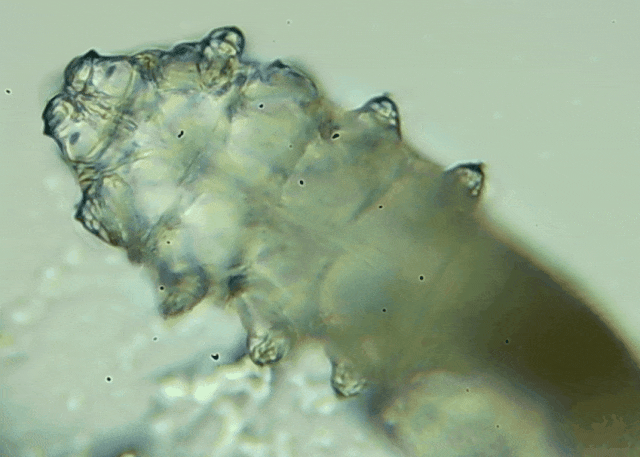

操作:医生会在每只眼睛的上下眼睑各拔3根典型睫毛,置于光学显微镜下观察。

报告解读:任一眼睑螨虫数量≥3 条 →阳性,需要干预。

优势:无创、快速、直观;当场给你看“活的”螨虫在睫毛上爬,视觉冲击堪比大片。